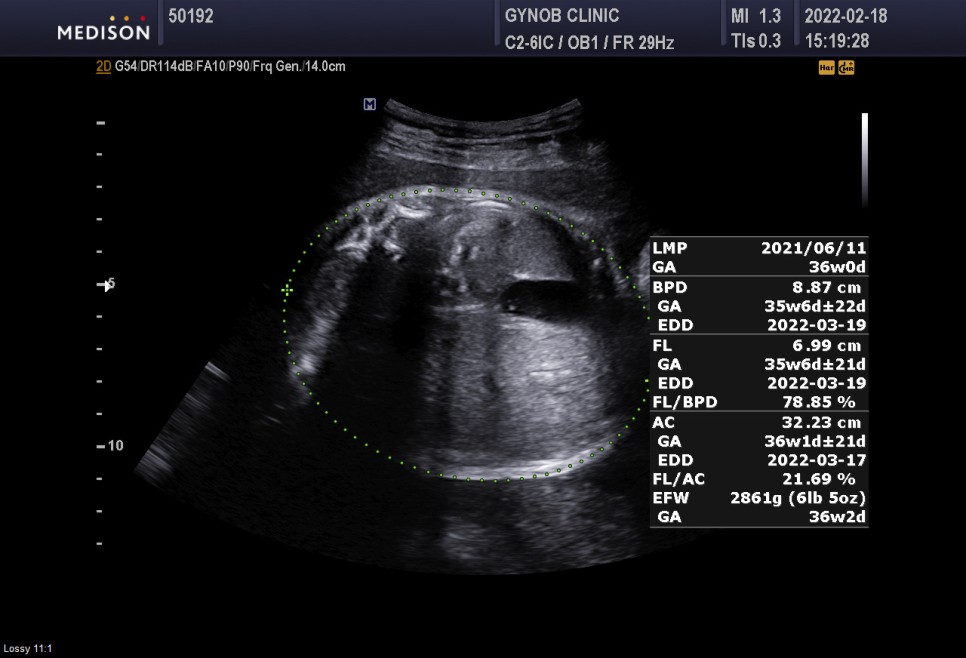

2022/02/18 임신 36주 차임 키 48.6kg 36주 현재 체중 56.2kg 합계 +7.6kg 증가

쭉쭉 체중은 2.86kg 조금 더 큰 편.

심박수 152bpm 정상

태반과 양수의 정상

경부제 대륜 1번 탯줄에 목을 1번 감고 있다는 뜻이다.너무 신경 안 써도 될 것 같아